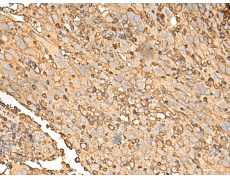

IHC positive control: |

Human cervical cancer and Human colorectal cancer |